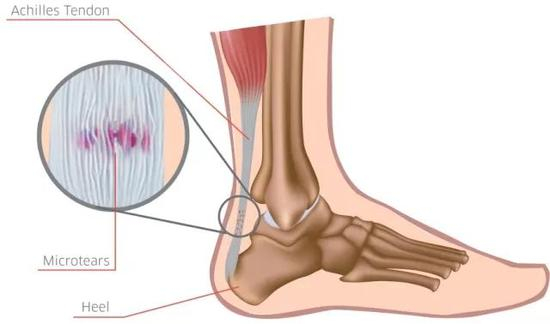

跟腱炎、足底筋膜炎、髌腱炎是几种最常见的跑步伤痛,主要表现为跟腱疼痛、足底疼痛和膝关节靠下一点的位置疼痛,这几类疼痛往往经久不愈,时好时坏。我们把这类伤痛虽然叫“炎”,但其实它们并非真正的炎症,因为在发生疼痛的部位往往检测不到炎症物质或者炎症细胞的存在,或者刚开始发生疼痛时的确是炎症,但后期逐步转变为慢性劳损,局部组织逐渐发生变性,也即组织的结构和特性发生了改变,比如组织变硬和钙化,我们称之为退变,或者退行性变。

因此,这类伤痛与其叫做炎症,还不如称为退变,而且这些退变往往发生在肌腱附着在骨骼的连接部位,比如跟腱附着在跟骨、髌腱附着在胫骨的部位,我们有时又把这类伤痛称为末端病。

所谓末端病就是指肌腱的末端附着在骨骼表面的连接部位。刘翔的跟腱就是这类问题,并最终导致刘翔被迫选择退役。末端病的本质是组织发生了变性和退变,而这种结构的改变很难治疗,几乎没有什么特别有效的方法,离心力量训练被认为可以改善肌腱组织的强度,从而缓解症状。